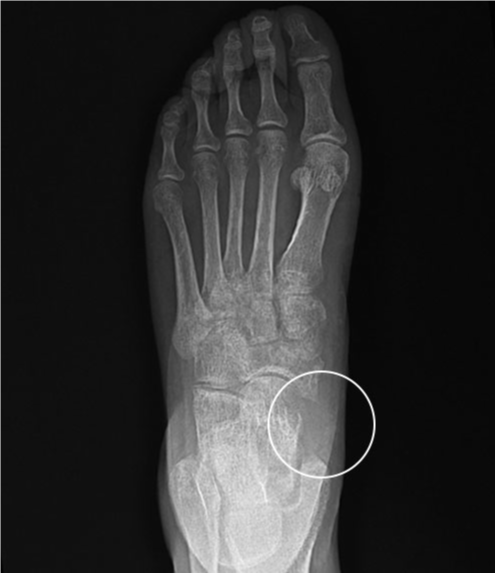

수술 전

2019.01.21

수술 후

2019.04.09

ㆍ환자 동의를 받은 자료이며, 이미지 사진은 실물과 다를 수 있습니다.